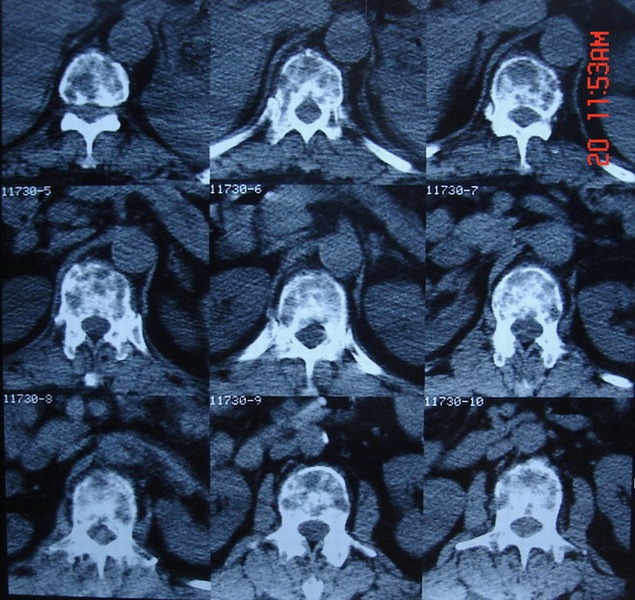

标题: CT7805:怀疑腰椎转移瘤 [打印本页]

男,65岁,临床诊断左肺ca,现腰痛半月余

自胸11至腰5椎体ct表现与上图相似

椎体内密度不均匀,见斑片状密度增高影,其内有更低密度区 部分皮质破坏 考虑 椎体转移瘤可能性大

椎体内密度不均匀,见斑片状密度增高影,其内有更低密度区 部分皮质破坏

考虑 椎体转移瘤可能性大